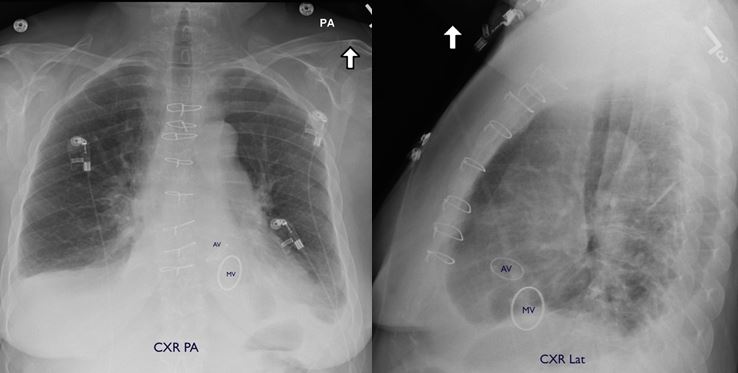

Fig. 2: Chest CT scan - dextroscoliotic. Spirometry: FEV 10.83L (37%), FVC 1.43L (50%), FEV1/FVC 58%, TLC 2.73L (62%), FRC 1.46L, DLCO 6.9 ml (31%), MIF 48 cmH20 (64%), MEF 52 cmH20 (37%)

The patient's resting room air Sp02 was 94%. Her pulmonary function test showed a mixed obstructive and restrictive pattern with severely impaired diffusion capacity (Fig. 2). She had a BP 116/82, HR 80 NRRR, RR 22 non-labored, height of 154 cm, weight of 74 kg, and BMI 31.1. Her lungs were clear. She had a 3-4/6 systolic murmur over the left parasternal border with occasional radiation to the axilla and no diastolic murmur. An echocardiogram (Fig. 3) showed a left ventricular EF of 65%, mild concentric LVH, moderate MR, severe AS, mild AI, and mild pulmonary hypertension. A right heart catheterization showed RAP 6, PAP 38/2, PCWP 18, LVEDP 10, AV gradient 30, and AVA 0.7 cm2. Her coronary arteries were free of significant angiographic stenotic or occlusive disease.

Fig. 5: Discharge CXR.